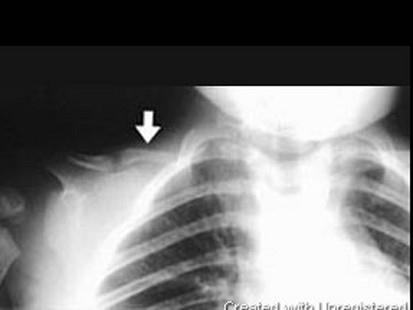

问题 男,2岁,发育迟缓,头颅软,请结合图像,选出最可能的诊断 ( )

选项 A、软骨发育不全 B、粘多糖病 C、颅锁骨发育不全 D、马方综合征 E、成骨不全

答案 C